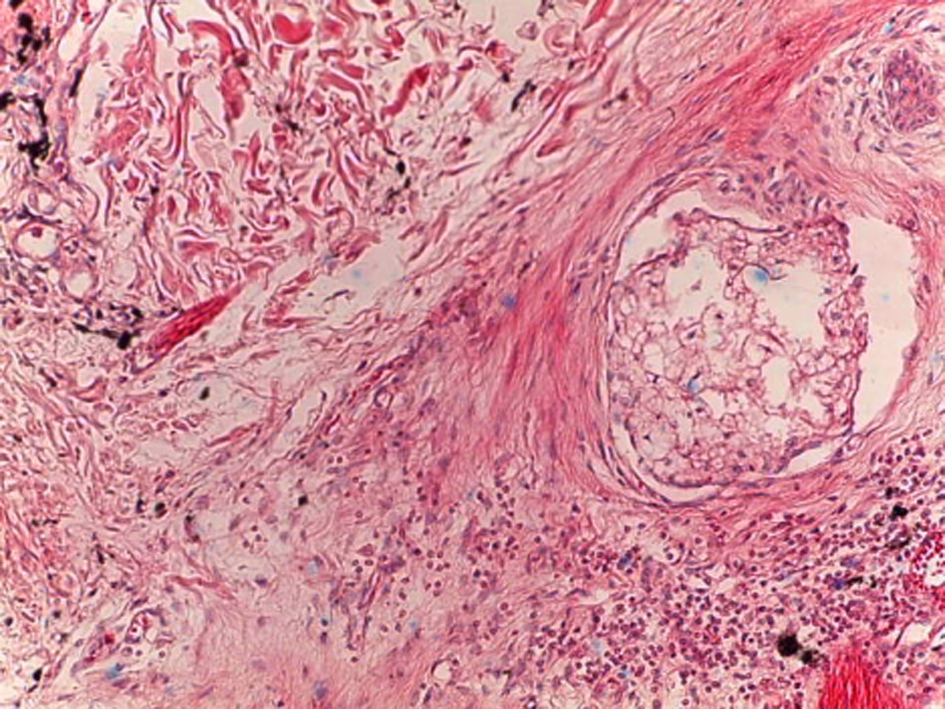

On the 10th day of the experiment, the pigment volume decreased slightly due to the presence of both resident macrophages and free phagocytes. The number of cells of the fibroblastic series increased significantly, and single fibrocytes were reported. These factors were associated with the presence of a severe inflammation at the early stages, and secondary tissue damage. In some cases, a thickening of the connective tissue fibers was observed. It was due to hyalinosis resulting in the formation of scars. According to the morphological structure, these scars were similar to keloid ones (Fig. 7).